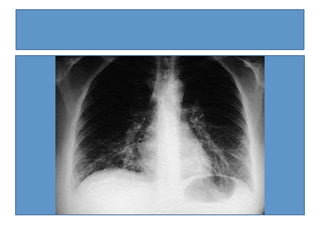

RX  y  lab  mycoplasma   Relleno  alveolar  del  >po  neumonía,  unilateral  (87%),  localizada  con  mayor  frecuencia  en  las  bases   pulmonares.   Atelectasias  lineales  de  grado  variable,  que  pueden  comprometer  a  todo  un  lóbulo  pulmonar.   Infiltrado  nodular  (infrecuente).   Adenopa_as  hiliares  (infrecuente)   Hemograma:  recuento  leucocitario  N  o  estar  moderadamente  elevado.   VHS  moderadamente  elevada.   Coombs,  ANA  y  VDRL    (+)